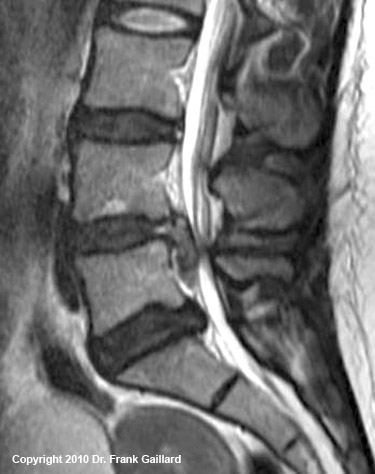

Large L4 disc herniationOn this page, I will teach you the basics of how to read your MRI images for the well-nigh typical causes of chronic back and/or leg pain.

mid-sagittalFigure 2 is a truthful mid-sagittal cutting through the lumbar spine, where the patient'due south belly button is to the left of the epitome and the back to the right.

There are ii main osseous (made of bone) structures that are clearly visible on the mid-sagittal view of a vertebra: the foursquare-shaped vertebral body of the vertebra (yellow outline) and the spinous process (blueish outline) of the posterior arch. The junction of the spinous process with the laminae make upward the anterior border of the posterior arch which besides forms the back of the central canal.This is covered with ligamentum flavum (Green L).

The extremely hyperintense space (almost pure white) between the vertebral bodies and posterior arch is the thecal sac (red T), which of course is filled with CSF. This structure may or may non completely fill the vertebral culvert, which is the space between the posterior vertebral trunk (Lead), pedicles, and lamina as represented by the black line I take drawn. Remember, this should measure twenty mm.

In the mid-sagittal view, the nervus roots of the cauda equina are typically not terribly visible (white-blue arrowheads) except as they go closer to their neuroforamina (non shown).

Situated between each of the v lumbar vertebral bodies, are the five lumbar discs (ruby-red outline & D) that carry about 80% of the axial-load of the torso and act every bit a pivot-point for trunk motion.

Clinically speaking, this view is ideal for picking upward a sometimes pain-producing condition called central stenosis, which occurs when the thecal sac gets squeezed and inflamed by a narrowed cardinal canal. (Learn more about central stenosis)